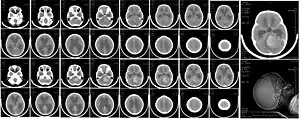

| CT scan, showing a tumorous mass in the posterior fossa, giving rise to obstructive hydrocephalus, in a six-year-old girl | |